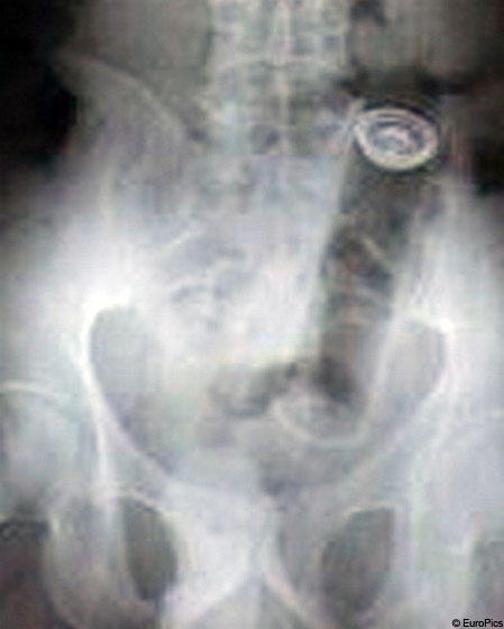

Nenavadni rentgentski posnetki

Rentgenski žarki so prvi omogočili pogled v ljudi, ne da bi jih bilo treba razre